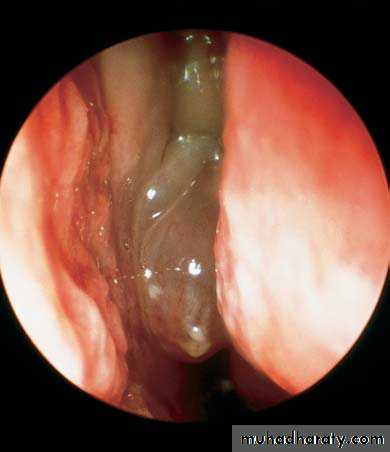

Another diagnostic modality for sinusitis is nasal endoscopyView into left nasal cavity demonstrates a polyp (P) extending from the middle meatus.

Purulent discharge from the middle meatus draining into the nasopharynx adjacent to the eustachian tube orifice.